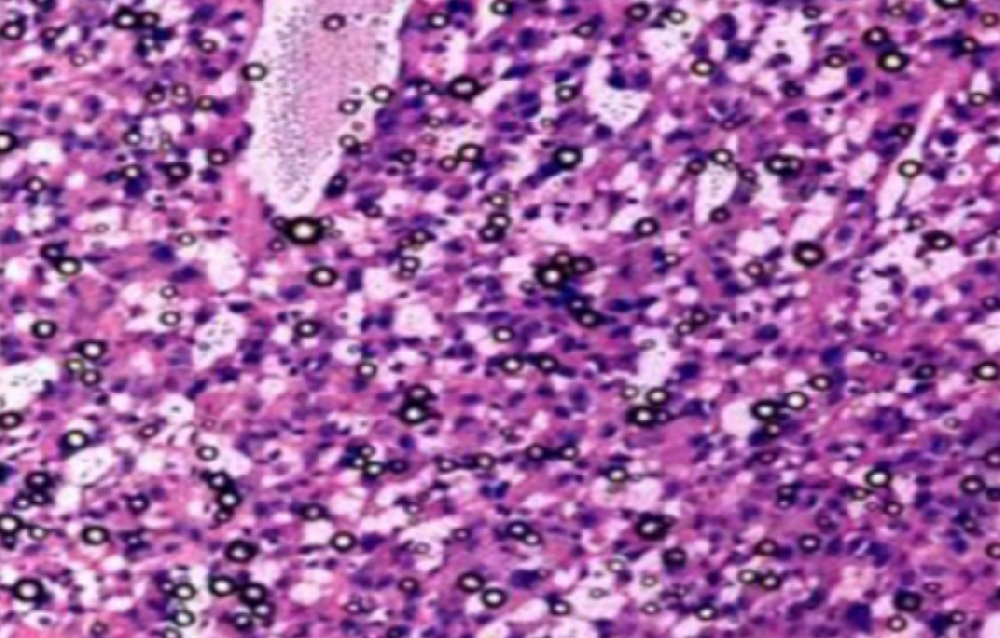

HE染色,全称苏木精-伊红染色法(Hematoxylin and Eosin staining),是最常见的组织切片染色技术之一,用于在显微镜下观察和分析组织或细胞的结构和形态。虽然HE染色是最常···